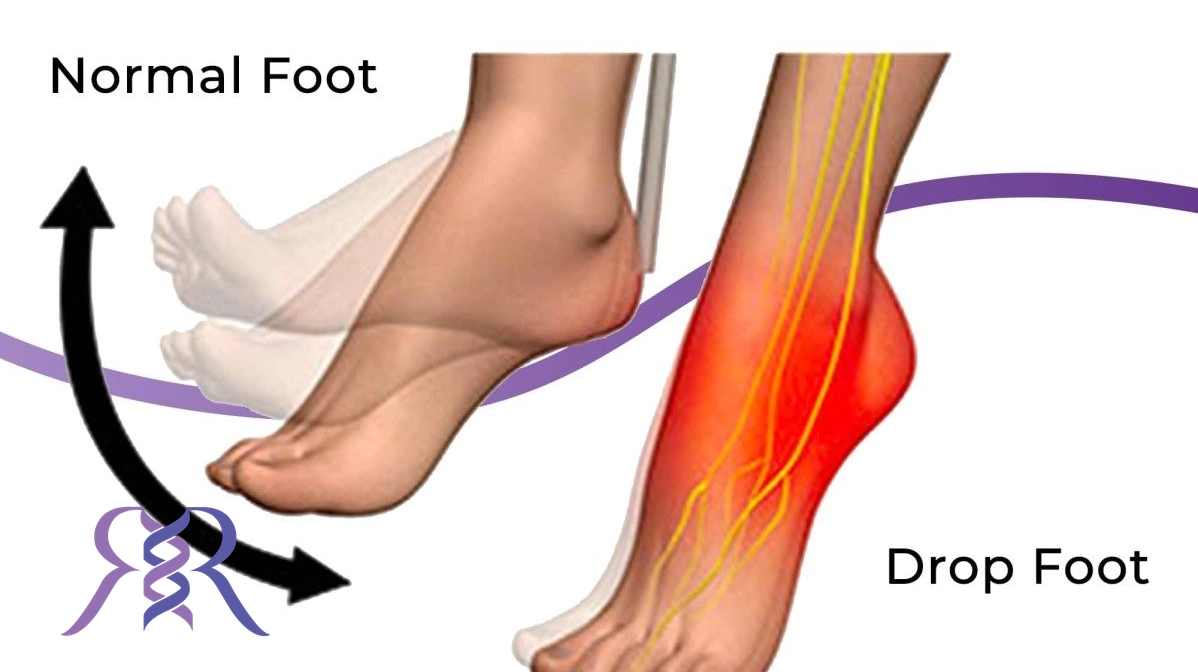

افتادگی مچ پا (که به آن پای صاف یا پای افتاده نیز گفته میشود) به وضعیتی اطلاق میشود که در آن عضلات و رباطهای اطراف مچ پا به طور غیرطبیعی ضعیف شده یا عملکرد خود را از دست میدهند. این امر موجب میشود که مچ پا به سمت پایین و بیرون حرکت کند و فرد در هنگام راه رفتن قادر به نگه داشتن مچ پا در موقعیت طبیعی خود نباشد. افتادگی مچ پا میتواند به دلایل مختلفی از جمله آسیبهای عصبی، اختلالات عضلانی، یا آسیبهای تاندونها ایجاد شود. علائم این وضعیت به طور معمول شامل ضعف و بیحسی در ناحیه مچ پا، دشواری در راه رفتن، و احساس عدم کنترل در حرکت مچ پا میباشد. در موارد شدید، این مشکل میتواند موجب ایجاد مشکلات در تعادل و افزایش خطر زمین خوردن شود.

افتادگی مچ پا یا “پای افتاده” میتواند به دلایل مختلفی ایجاد شود که معمولترین آنها شامل آسیب عصبی، ضعف عضلانی، و مشکلات ساختاری هستند. یکی از علل اصلی این وضعیت، آسیب به اعصاب است که میتواند به دلایل مختلفی مانند سکته مغزی، آسیبهای تروماتیک (مانند شکستگی یا آسیبهای ورزشی) یا دیابت رخ دهد. آسیب به اعصاب میتواند منجر به از دست دادن کنترل عضلات پا و ناتوانی در بلند کردن مچ پا شود. ضعف عضلانی، به ویژه در عضلات مچ پا و ساق پا، نیز یکی دیگر از علل رایج افتادگی مچ پا است که ممکن است در اثر بیتحرکی، کهولت سن یا بیماریهای خاص مانند ام اس یا نوروپاتی ایجاد شود. علاوه بر این، مشکلات ساختاری مانند عدم تراز مناسب مفصل یا مشکلات مادرزادی در استخوانها و مفاصل میتواند باعث افتادگی مچ پا شود. این وضعیت ممکن است با علائم مختلفی مانند مشکل در راه رفتن، سایش کفشها و ضعف در حفظ تعادل همراه باشد.

افتادگی مچ پا میتواند علائم و مشکلات مختلفی را در عملکرد پا و مچ ایجاد کند. این وضعیت به طور معمول با ضعف عضلات و اختلال در کنترل حرکات مچ پا همراه است که به مشکلاتی در راه رفتن و حفظ تعادل منجر میشود. در ادامه، برخی از علائم شایع این مشکل آورده شده است:

یکی از اولین علائم افتادگی مچ پا، ضعف در بلند کردن مچ پا به سمت بالا است. این مشکل به دلیل ضعف عضلات دوشاهده کننده (دستور دهنده) که مسئول حرکت مچ پا هستند، رخ میدهد و موجب میشود فرد قادر نباشد مچ پا را به طور طبیعی در حین راه رفتن بالا بیاورد.

افراد مبتلا به افتادگی مچ پا ممکن است دچار مشکل در راه رفتن شوند، زیرا توانایی حرکت مچ پا به طور مناسب وجود ندارد. این مشکل میتواند باعث کشیده شدن انگشتان پا روی زمین یا لگد زدن به خود هنگام راه رفتن شود، که باعث کاهش سرعت و ناهماهنگی در گام برداشتن میشود.

افراد مبتلا به افتادگی مچ پا ممکن است احساس بیحسی یا سوزش در ناحیه مچ پا یا ساق پا داشته باشند. این علائم میتواند ناشی از آسیب به اعصاب یا فشار بر عصبها باشد که بر عملکرد طبیعی عضلات تأثیر میگذارد.

افتادگی مچ پا میتواند باعث کاهش تعادل شود، زیرا فرد در حرکت مچ پا و پاهای خود به درستی کنترل ندارد. این مشکل میتواند خطر زمین خوردن یا افتادن ناگهانی را افزایش دهد.

به دلیل عدم توانایی در حرکت طبیعی مچ پا، افراد ممکن است برای جبران ضعف خود، راه رفتن با گامهای بلندتر یا تغییر در زاویه پا را انتخاب کنند. این تغییرات ممکن است به مشکلات جدیدی مانند درد زانو، کمر یا ران منجر شوند.

افتادگی مچ پا به طور معمول به دلیل مشکلات عصبی، تاندونها یا عضلات رخ میدهد و در صورت عدم درمان، میتواند به مشکلات بیشتری در عملکرد حرکتی بدن منجر شود.